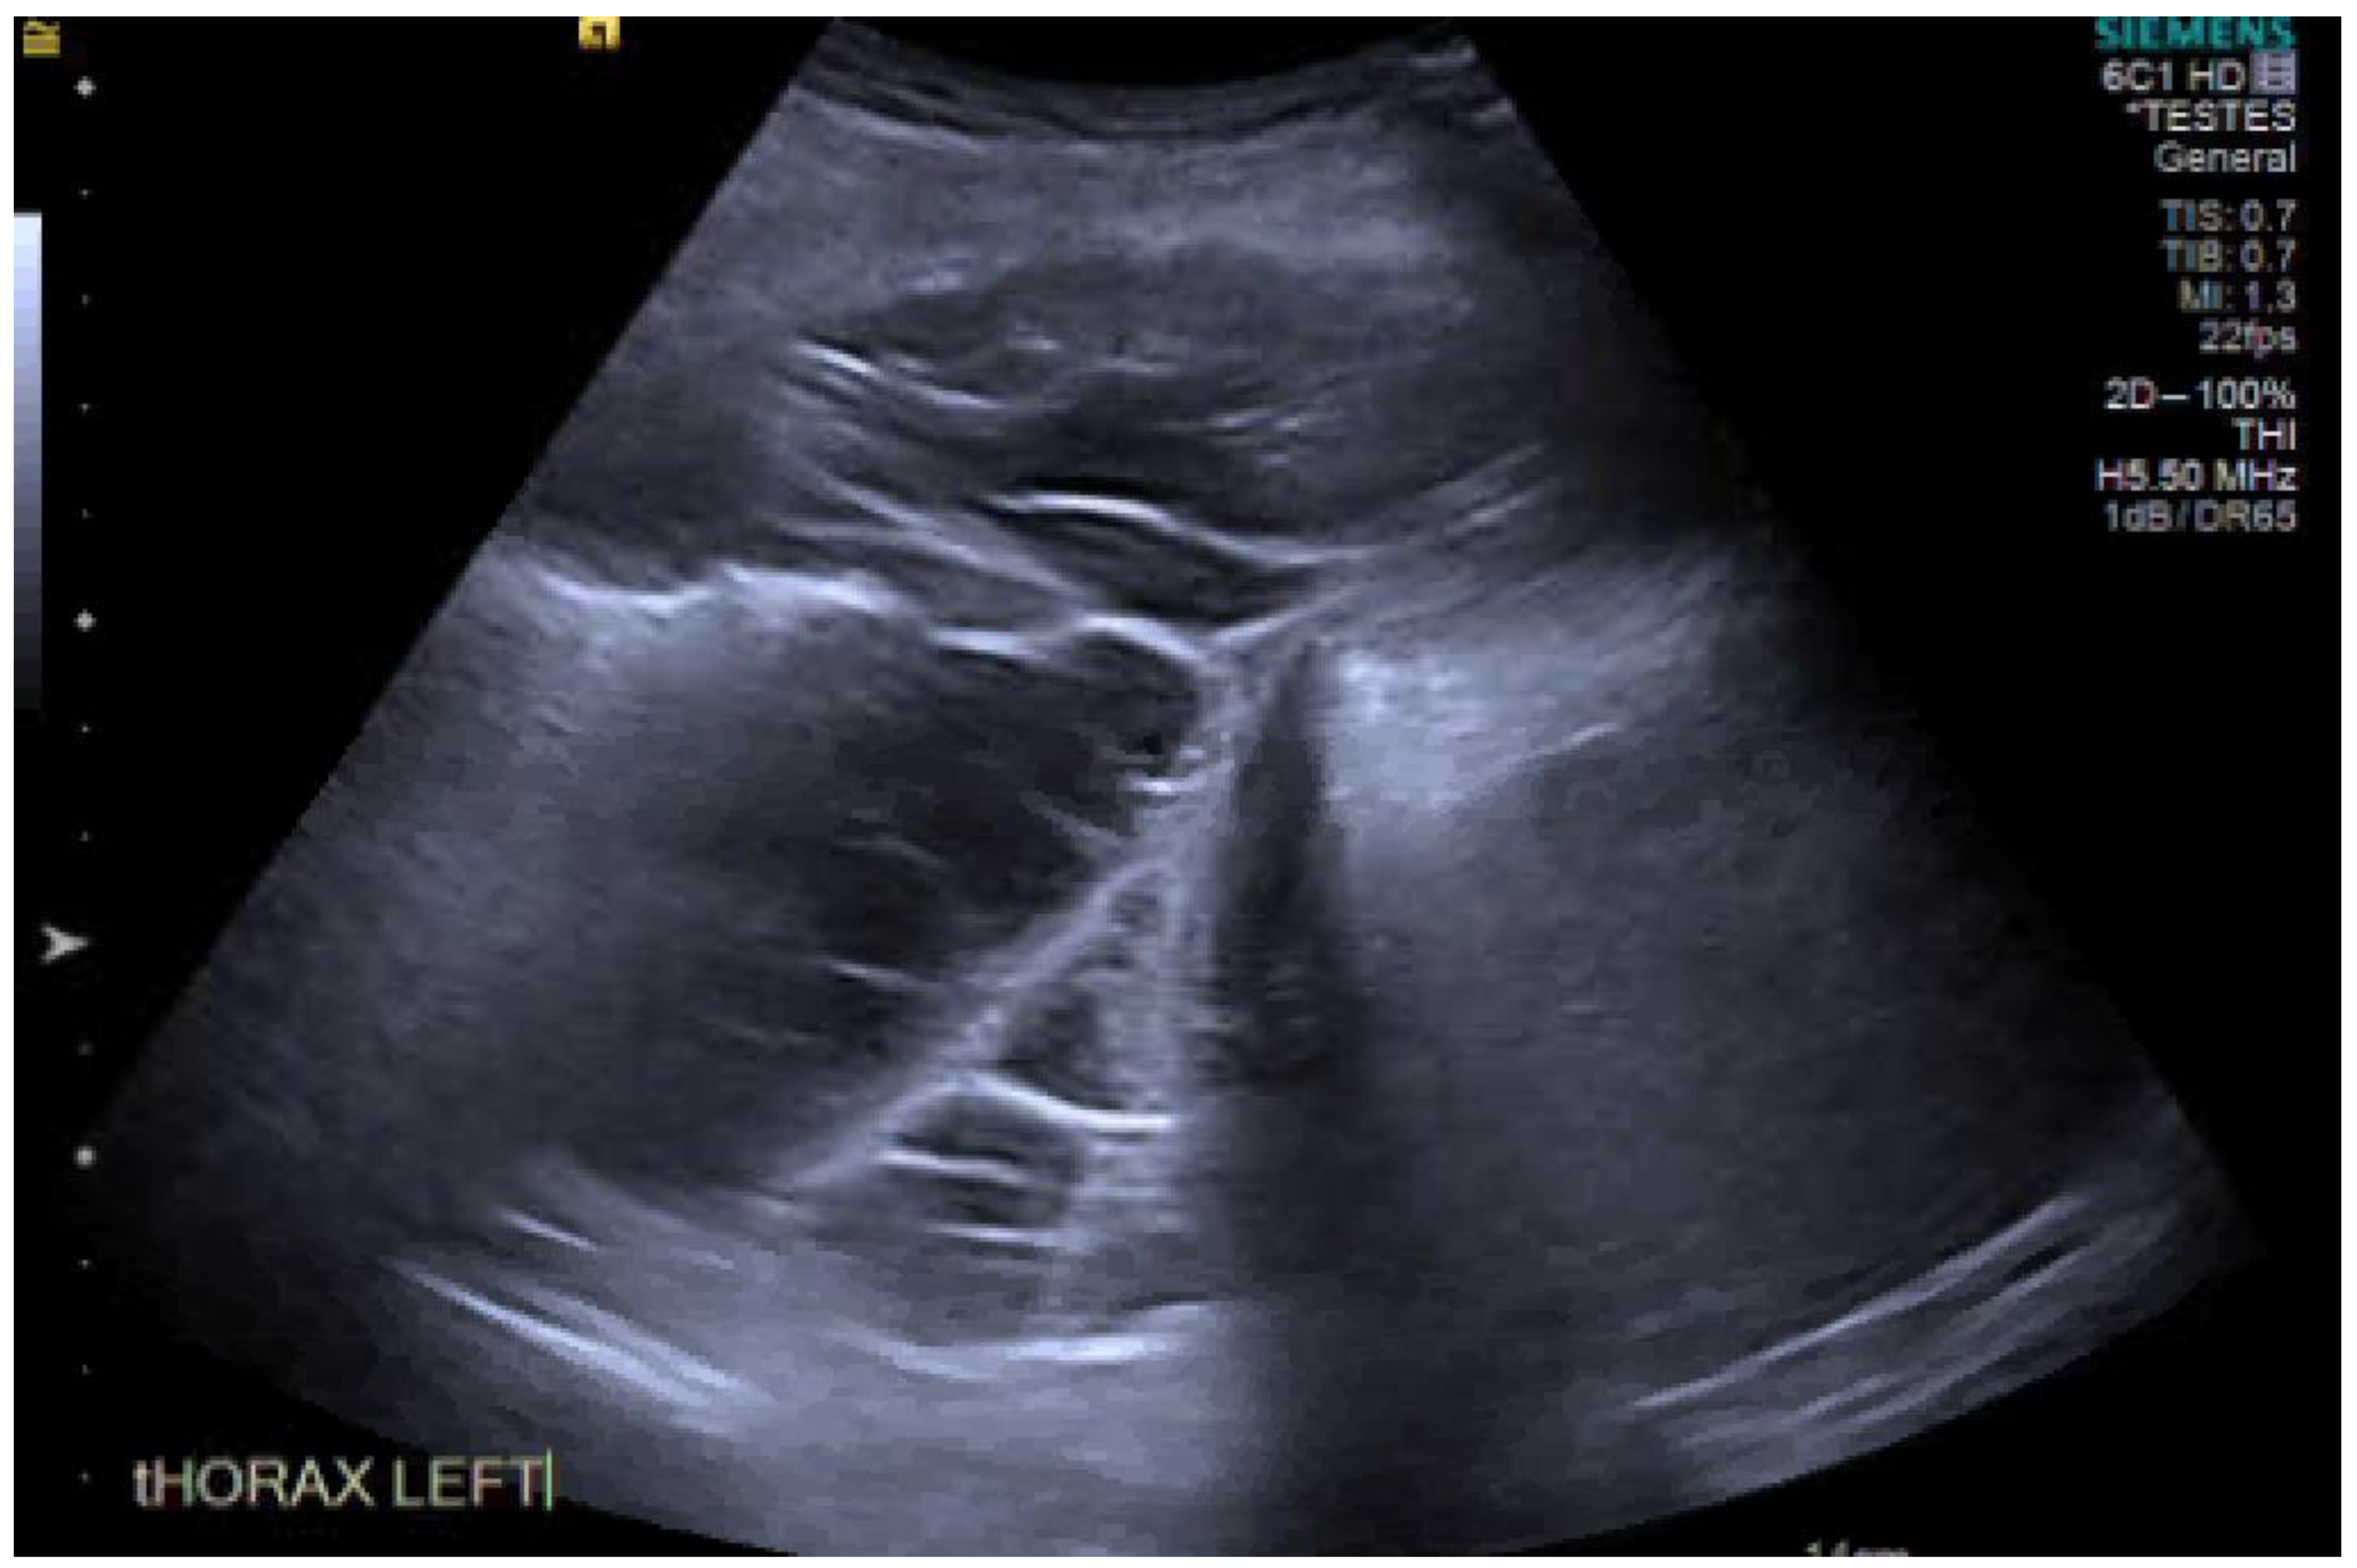

13. Ultrasound

- Gryminski, J.; Krakówka, P.; Lypacewicz, G. The Diagnosis of Pleural Effusion by Ultrasonic and Radiologic Techniques. Chest 1976, 70, 33–37. [Google Scholar] [CrossRef]

- Motogna, M.K.; Maratou, K.; Paianid, I.; Soldatos, T.; Antipa, E.; Tsikkini, A.; Baltas, C.S. Application of color Doppler ultrasound in the study of small pleural effusion. Med Ultrason. 2010, 12, 12–16. [Google Scholar]

- McLoud, T.C.; Flower, C.D. Imaging the pleura: Sonography, CT, and MR imaging. Am. J. Roentgenol. 1991, 156, 1145–1153. [Google Scholar] [CrossRef]

- Banka, R.; Skaarup, S.; Mercer, R.; Laursen, C. Thoracic ultrasound: A key tool beyond procedure guidance. In Pleural Disease (ERS Monograph) [Internet]; Maskell, N.A., Laursen, C.B., Lee, Y.C.G., Rahman, N.M., Eds.; European Respiratory Society: Sheffield, UK, 2020; pp. 73–89. [Google Scholar] [CrossRef]